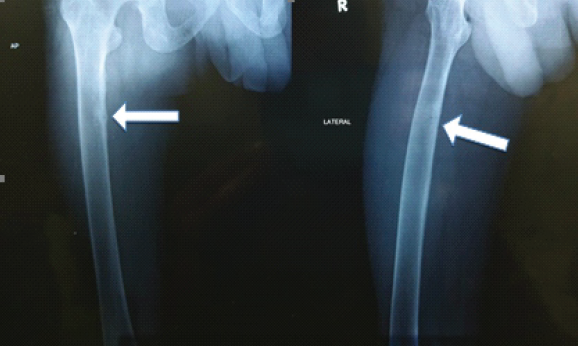

A 35-year-old man presented to our hospital for the evaluation of stress fracture of neck of the femur. He was previously healthy except for lower back ache which bothered the patient every now and then during the previous 4–5 years. His aches and pain had worsened over the past 1 year, and he even developed pain in the hip while walking for which he was seen in the orthopedic outpatient department and the patient was diagnosed to have osteoporosis with stress fracture of the neck of femur on both sides. During his evaluation for stress fracture, he was found to have hypophosphatemia, and hence, the patient was referred to internal medicine for further evaluation. (Fig. 1)

Figure 1: X-ray of right femur showing looser zones (white arrows) indicating pseudo fractures.

Fractional excretions of calcium and phosphorus were 1.84% and 44.1%, respectively. The serum 25(OH) vitamin D level was 30.5 ng/mL. His magnetic resonance imaging and computed tomography scan of both hip joints showed an acute stress fracture of the right femoral neck and findings consistent with pseudo fractures, i.e., Looser’s zone of osteomalacia, which are suggestive of metabolic bone disease.